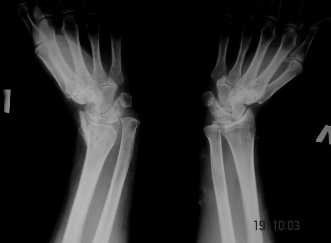

Уважаемые коллеги! Обратилась женщина, 55 лет. Травма 3 месяца назад, лечилась по месту жительства (Рис.1). Косорукость, боли, ограничение движений.

Досняли - рис.2-6. Хотелось-бы услышать мнения об объеме операции. С уважением, Юрий Алексеевич Булахтинглавный травматолог Камчатского Военно-морского госпиталя

u pazientki po nauchnomu ulna abutment/impingment syndrome posle posttraumaticheskogo ukorochenia radiusa

na rengene znachitelnoe ukorochenie radiusa, sustavnaia poverchnost naklonena dorsalno chresmerno , chetko vidno nekongruentnost DRUJ - distalnogo radioulnarnogo sustava ,ulna prosto vtikaetsia v triquetrum .